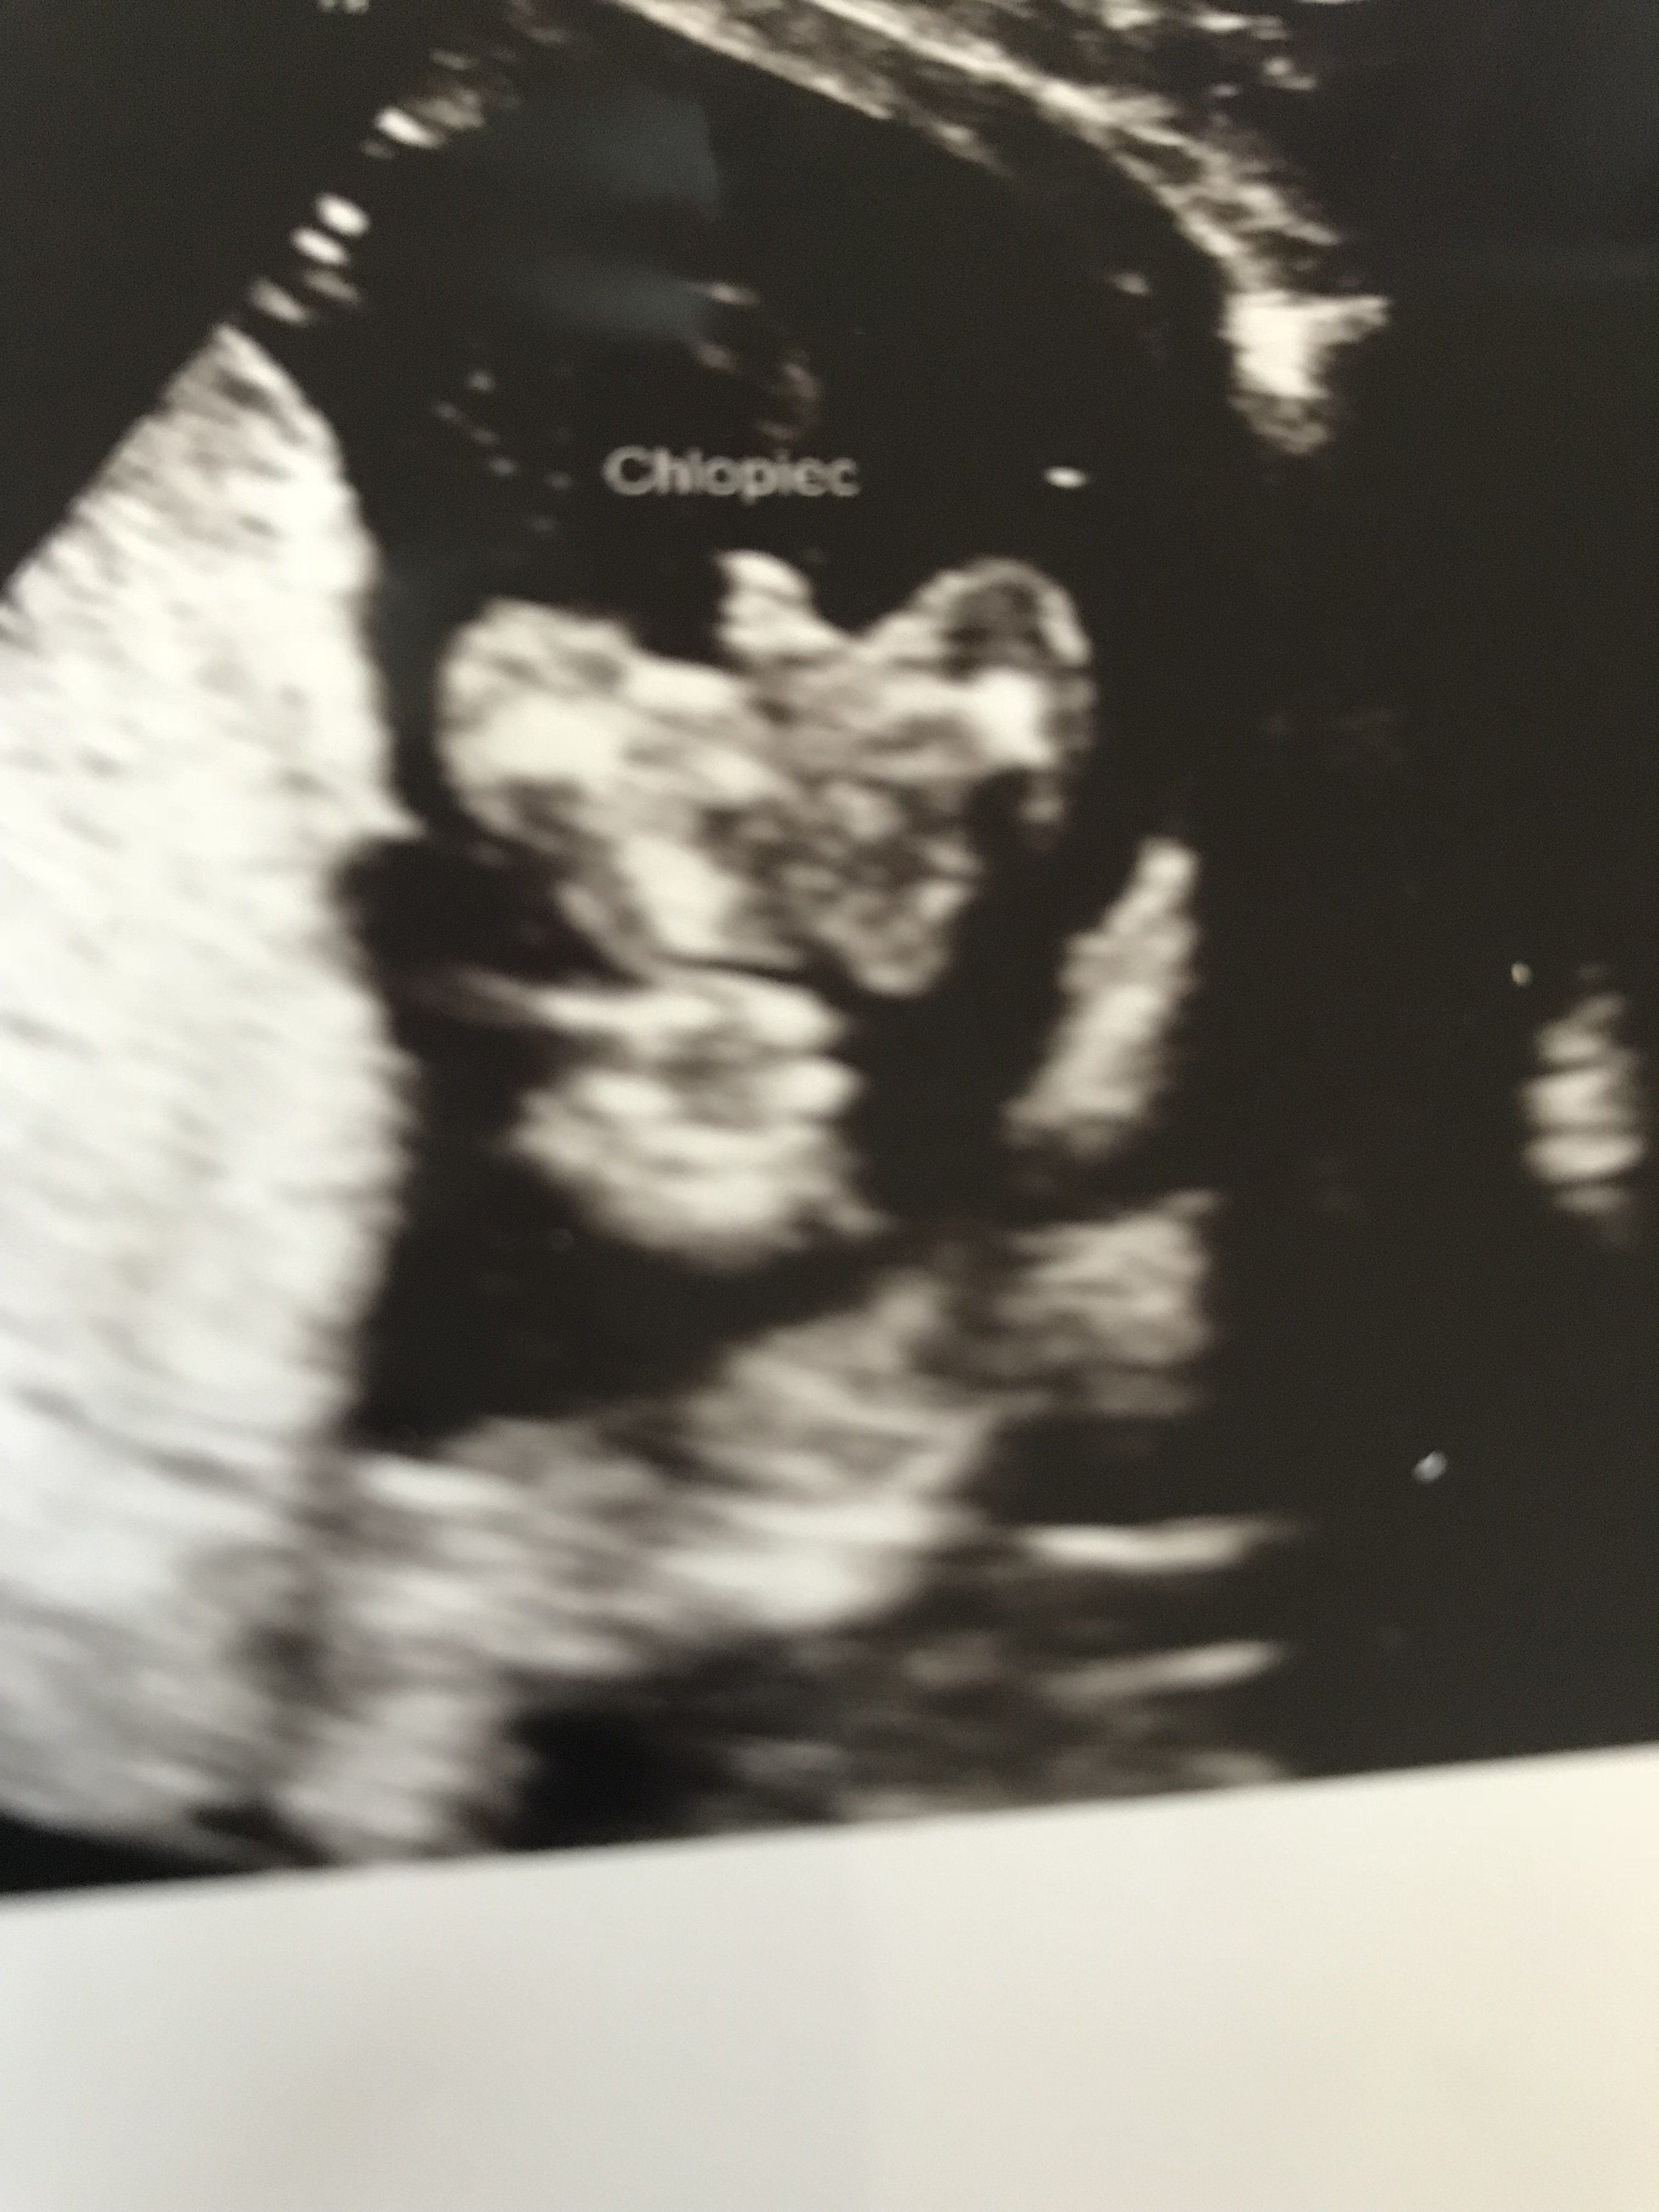

Witam w 19 tygodniu ciąży dowiedziałam się ze będę miała dziewczynkę w 20 tyg okazało się jednak , że to chłopak. Sama już nie wiem bo na jednym usg widać na pewno dziewuche a na drugim chłopca. Może to pempowina ?? Może ktoś mi pomoże rozwiązać ta zagadkę

w poniedziałek mam kolejna wizytę ciekawa jestem co teraz powie

mimo tego ze na każdej wizycie mówi ze będzie trzeci syn ja i tak czekam do porodu a może sie myli

najwazniejsze ze jest zdrowe i ja czuje się nienajgorzej